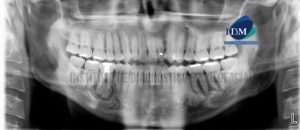

Paciente masculino de 42 años de edad es referido al Instituto de Diagnóstico Maxilofacial (IDM) para evaluación general. En la reconstrucción panorámica (Figura 1)se observa